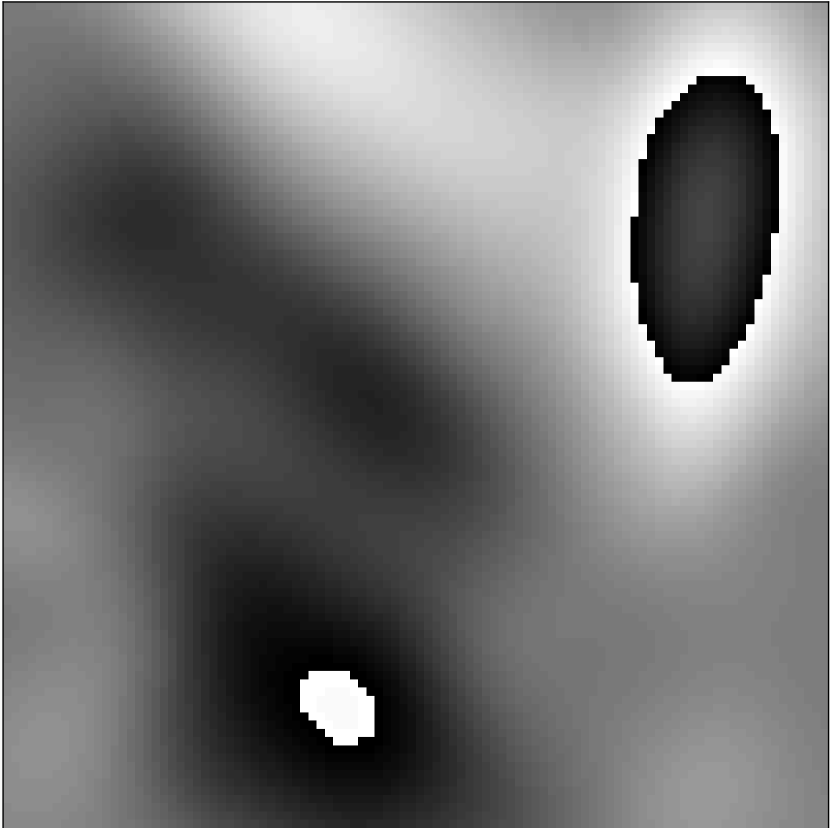

The simplest Gibbs simulation could be accomplished by cropping the k-space representation of a high-resolution image. However, in practice MR acquisitions are affected by many factors other than the Gibbs phenomenon. We simulate a subset of these effects. Figure 1 shows a flowchart of the simulation pipeline. The simulation begins with raw grayscale ImageNet image (converted via BT.601 color standards), resized to a standard size of 256×256256256256\times 256 using bilinear interpolation [30]. The simulation then randomly flips and/or transposes the image, each with a 50% probability. After flipping and transposing, the simulation proceeds to the random phase step. The random phase simulation generates a random set of Gaussian radial basis functions for each simulated image - this is described in detail in Appendix A. An example of simulated phase compared to a true in vivo phase case is shown in Figure 3.

Simulated Phase

In Vivo Phase

Figure 3: Examples of phase from in vivo diffusion-weighted data and the simulations used for network training. Phase maps can have substantial variations that must be considered when applying partial Fourier imaging.

The random phase simulation requires a number of probabilistic parameters for specifying the distribution of the simulated phase - these are reported in the appendix.

When Bssubscript𝐵𝑠B_{s} and S𝑆S are not too large, psim(𝒓)subscript𝑝sim𝒓p_{\textit{sim}}(\bm{r}) will typically be smooth as in real application settings; however, sharp changes can also occur during training when basis function centers are near each other. As a further form of data augmentation, we include a 1% probability that no phase at all is simulated. Figure 3 shows an example of simulated phase compared to real phase from in vivo data. For our experiments, we used λS=12subscript𝜆𝑆12\lambda_{S}=12, λB=15subscript𝜆𝐵15\lambda_{B}=15, μz=64 pixels2subscript𝜇𝑧64superscript pixels2\mu_{z}=64\text{ pixels}^{2} σz=100 pixels2subscript𝜎𝑧100superscript pixels2\sigma_{z}=100\text{ pixels}^{2}, μa=0°subscript𝜇𝑎0°\mu_{a}=0\degree, and σa=5°subscript𝜎𝑎5°\sigma_{a}=5\degree. We set rmin,jsubscript𝑟min𝑗r_{\textit{min},j} and rmax,jsubscript𝑟max𝑗r_{\textit{max},j} to restrict the center of the Gaussian basis function to the image support in the j𝑗jth dimension.